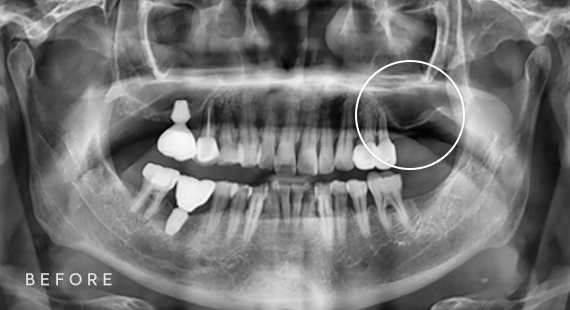

임플란트

충치치료